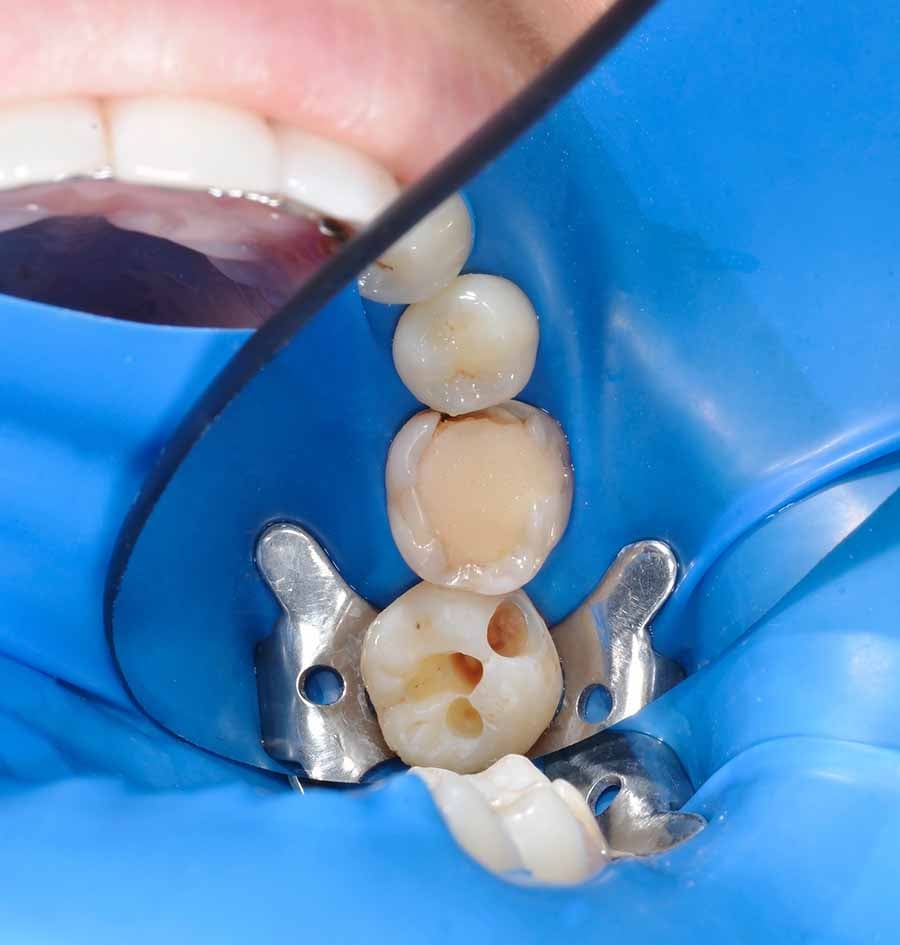

Calzas Dentales Blancas

Las calzas dentales blancas son una opción popular para mejorar la apariencia dental. Están diseñadas para que coincidan con el color natural de los dientes, proporcionando un aspecto natural y atractivo.